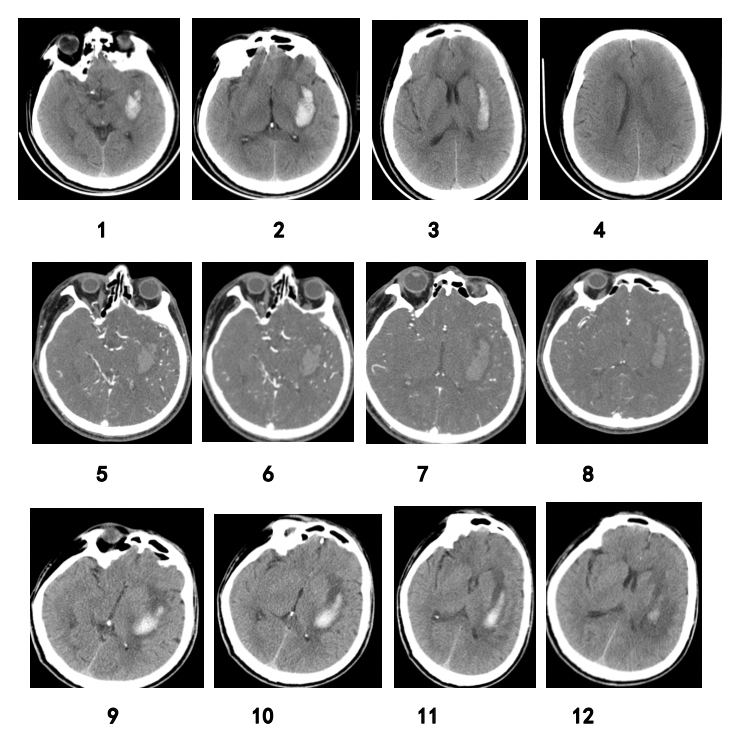

Predictive value of imaging manifestations of supratentorial hemorrhage in hematoma enlargement and clinical prognosis

Intracerebral hemorrhage (ICH) is an important cause of death and disability. This study aimed to explore the imaging indicators identifying hematoma expansion in primary ICH and to provide a basis for its clinical treatment.

Hematoma expansion was evaluated by plain computed tomography (CT) scan and multi-detector-row CT angiography (MDCTA).

This study included a total of 203 patients with intracerebral hemorrhage. The size of the hematoma at the time of admission was 32.5–92.3 ml (mean: 45.5 ml). Original or reconstructed MDCTA images with contrast extravasation were available in 35 (17.2%) cases. Patients were divided into two groups based on whether or not hematoma expansion had occurred: the hematoma expansion group (n = 87) and the no hematoma expansion group (n = 116). Percentages of patients with spot signs in the two groups were 37.93% and 3.45%, respectively, and percentages of those with spot sign ± blend sign ± black hole sign ± island sign (%) were 48.30% and 1.72%, respectively, with statistically significant differences. The sensitivity, specificity, and positive and negative predictive values of hematoma enlargement were 37.93%, 98.27%, and 94.29% and 67.86%, respectively. The sensitivity, specificity, and positive and negative predictive values of blend density sign ± irregular sign in predicting hematoma enlargement in ICH patients were 97.7%, 76.7%, and 75.9% and 97.8%, respectively.

Blend density sign ± irregular sign can be used as substitute signs. The more irregular and uneven density the hematoma, the more likely it is that the hematoma will be enlarged.